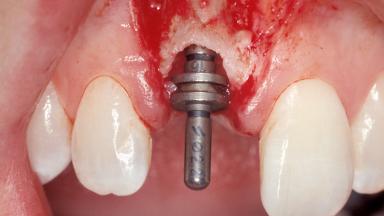

Immediate Placement of an Implant in a Maxillary Right Central Incisor Site

A 30-year-old female patient was referred to the office for the treatment of tooth 11. Her chief concern at the initial visit was to inquire, “Why is my tooth pink?” Upon clinical examination, it was determined that tooth 11 had a previous history of trauma and that the clinical crown had become noticeably pink in color as a result of internal resorption. This diagnosis was confirmed radiographically, indicating a large radiolucency involving the central and distal portions of the clinical crown. It was determined that restoration of this tooth was not possible, and that extraction was indicated. The presence of a mid-line diastema, which the patient wanted to reproduce, directed the treatment plan for tooth replacement utilizing a dental implant.

# of Implants 1

Type of Implants One-Piece|Reduced-Diameter

Bone Augmentation Horizontal|Simultaneous

Augmentation Materials Autogenous chips|Membrane

Placement Protocol Immediate implant placement

Tooth Site Maxillary incisor or canine